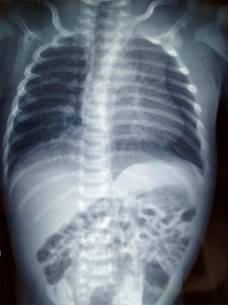

Al nacimiento se identificó malformación a nivel del tórax, con agenesia del pectoral derecho y amastia (Figura 1), así como sindactilia/braquidactilia de la mano derecha (fusión del tercer, cuarto y quinto dedos/anular, dedo del medio y el menique o dedo auricular) (Figura 2). No se detectó alguna otra malformación en el resto de la exploración física. En la radiografía de tórax no evidenciaron alteraciones óseas (Figura 3). Con los datos clínicos y de imagen se concluyó un síndrome de Poland grado I.